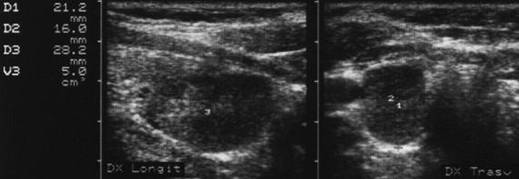

Carcinom midUlar

Lob stang, proiectie trasversala si longitudinala

Barbat de 55 ani. Formatiune nodulara voluminoasa ce ocupa 2/3 din lobul stang, hipoecogena, neomogenea, de 20 x 23 x 44mm(10 cc). Citoaspirata ecoghidata: carcinom midolar. Confirmat histologic.

Scintigrafia si CT aceluiasi pacient, metastaza laterocervicala stg ce impinge traheea spre dr.